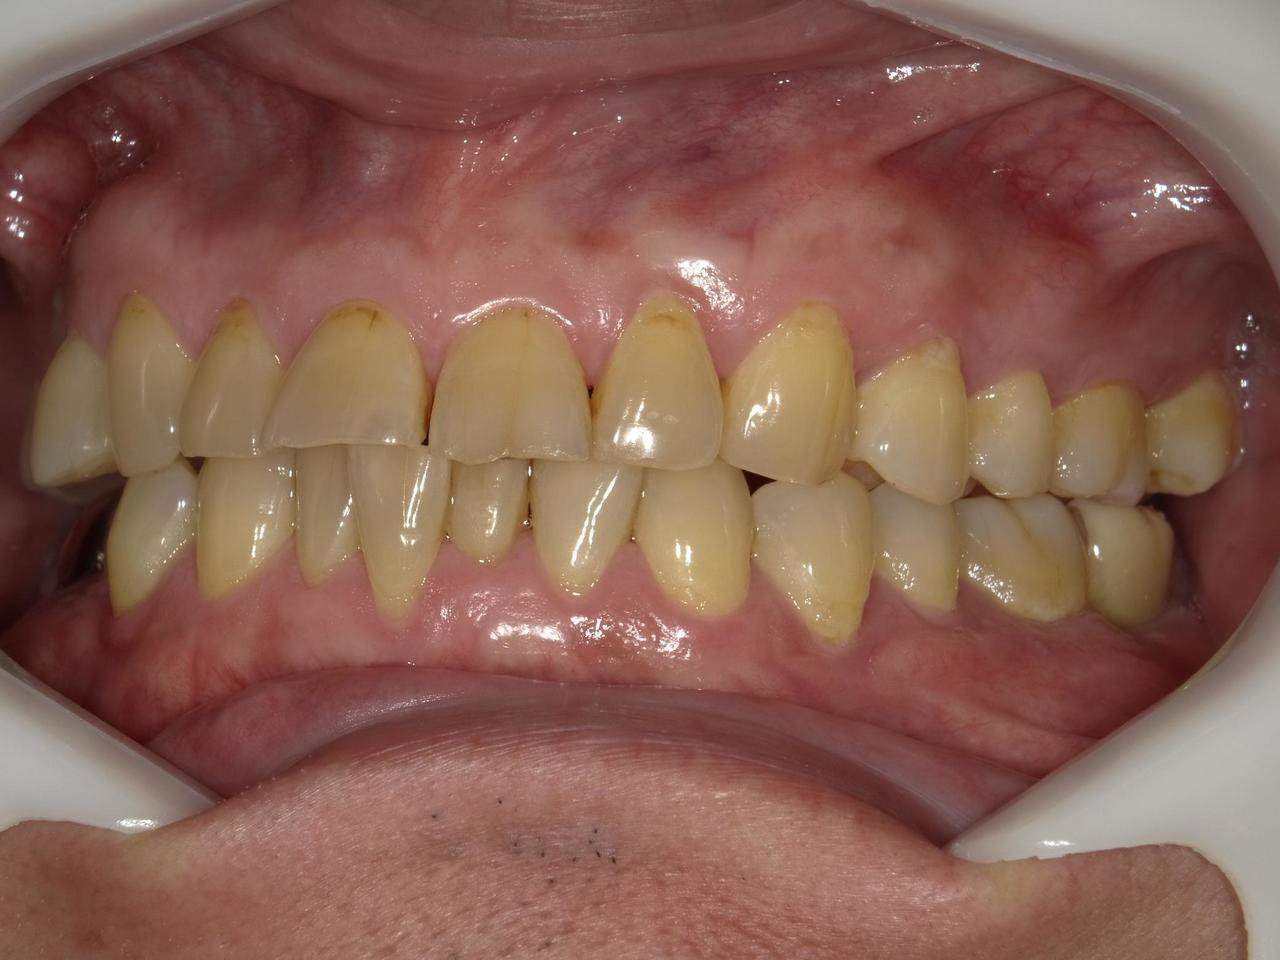

Before

枚方市のインプラントの症例

K・Y 様 女性 50代

症状としては、右上6番の歯が歯周病のため、自然に抜けてしまった。

治療法としては、歯周病により、右側6番の上顎骨が吸収して、2mm程度の骨しか残っていなかったため、サイナスリフトが必要であった。通常のサイナスリフトだと時間(時間的には1年から1年半程度かかると考えます。)と費用がかかり、患者様への時間的、肉体的、金銭的負担が大きくなることを考慮して、今回は、インプラントの種類としては、エクストラワイドショートインプラント、術式としては、デンサーバーを使用したグラフトレスサイナスリフトを選択しました。最終補綴物はジルコニアで仕上げています。

結果としては、高度に吸収した上顎骨に対するインプラント治療であったが、グラフトレスサイナスリフトを行うことで、短時間(2か月半程度)で治療を終えることができた。また、サイナスリフトによくある術後合併症である上顎洞炎を起こすことなく、患者様への肉体的な負担を抑えた治療を行うことができた。また、上顎右側6番にインプラント治療できたことにより、咬合が安定するとともに、歯周病にり患している上顎の他の歯に対する負担を少なくすることができた。